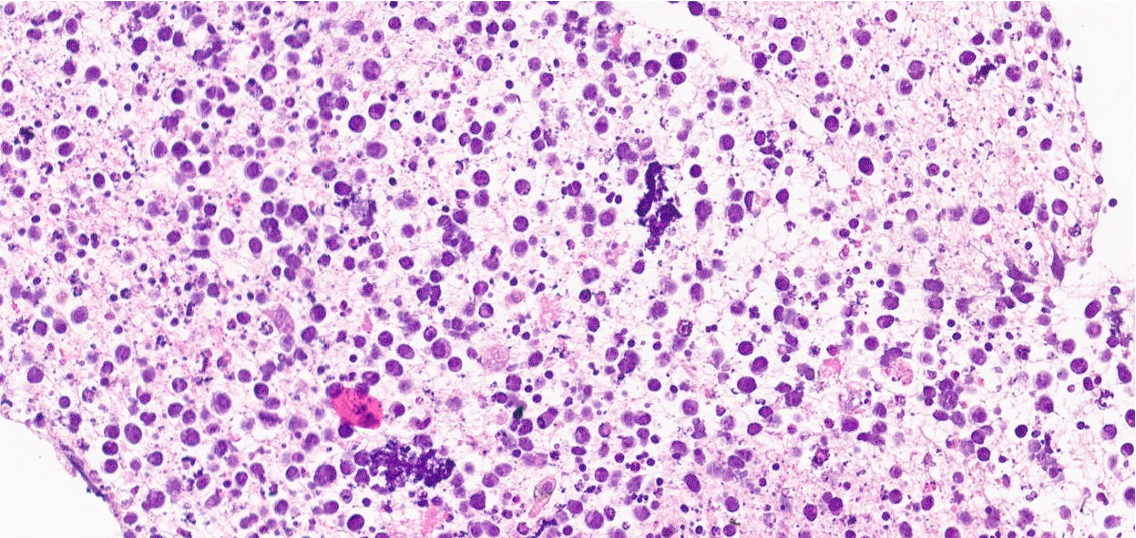

This mass was suspected to be malignancy then bronchoscopy with lymph node biopsy and bone marrow biopsy were done. Lymph node tissue histopathology reported suggestive of diffused large B-cell lymphoma. Bone marrow tissue histopathology reported hypercellularity involved by high-graded mature B-cell lymphoma leading to diagnosis of Non-Hogkin's lymphoma stage IV and promptly CHOP regimen chemotherapy treatment.

This mass was suspected to be malignancy then bronchoscopy with lymph node biopsy and bone marrow biopsy were done. Bronchoscopy with mediastinal lymph node biopsy were done. Lymph node tissue histopathology reported malignant small round cell tumor with positive for CD20, CD45, BCL-6 and C-MYC immunohistochemistry, suggestive of diffused large B-cell lymphoma. Finally, bone marrow tissue biopsy was done and histopathology reported hypercellularity involved by high-graded mature B-cell lymphoma leading to diagnosis of Non-Hogkin's lymphoma stage IV and promptly CHOP regimen chemotherapy treatment